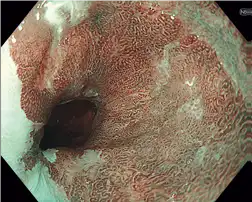

NBI正常聚焦 NBI近焦

高倍率和双焦点

当通过简单的内窥镜开关进入近焦点模式时,GIF-EZ1500可提供高放大倍率*,从而可以更好地观察细节。高放大率和宽景深的结合,即使从切线方向,无论对象是否运动,都可以在整个视场中获得更清晰,更详细的成像。结合成熟的NBI技术,GIF-EZ1500的先进光学器件旨在帮助进行准确,高置信度的光学诊断。(来源:成贯仪器)